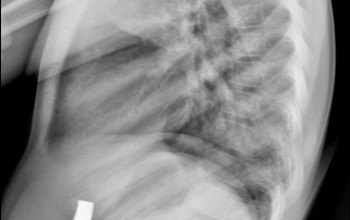

Wyposażyliśmy pracownię w cyfrowy detektor z oprogramowaniem posiadającym funkcję skalometrii (Stitching), dzieki której możliwe jest wykonanie badania telemetrycznego RTG całych kończyn długich i całego kręgosłupa a następnie uzyskanie obrazu diagnostycznego obejmującego razem kilka części anatomicznych połączonych w całość.

Skalometrie stosuje się w diagnostyce schorzeń ortopedycznych